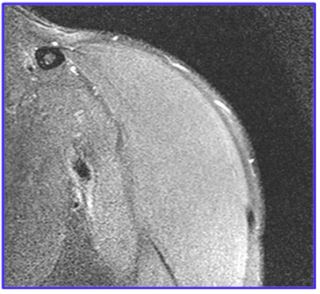

A 29-year-old man presented with a one-year history of left shoulder pain, which increased with range of motion and further aggravated on gym training. The patient underwent Magnetic Resonance Imaging (MRI) of the shoulder, which revealed significant hypertrophy of the coracohumeral and superior glenohumeral ligaments on normal grey scale images (Figure 1). We performed cartigram (T2 relaxometry) and the necessary post-processing techniques such as colour mapping (Figure 2a) and T2 values (Figure 2b) on coronal plane (where maximum glenohumeral cartilage can be seen) with a 1.5 Tesla MRI machine (SIEMENS MAGNETOM Avanto, Siemens Medical Solutions USA, Inc., PA, USA).

Figure 1: : Proton density images -coronal plane.